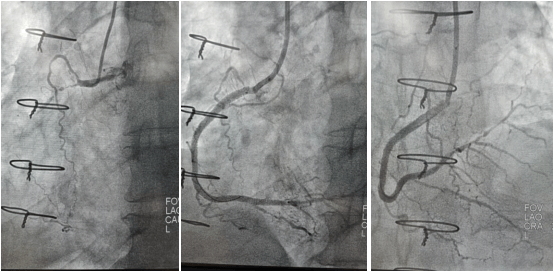

2022年9月16日行冠脈造影術,造影結果示:左主干末端99%狹窄,LAD近段100%閉塞,LCX開口及近段95%狹窄,乳內動脈-左前降支血管通暢,RCA近段100%閉塞,大隱靜脈橋血管未見,考慮閉塞。

心血管病院吳棟梁院長、CCU李新國副主任、心血管內科二病區趙娟副主任、王端樂主治醫師、宋睿主治醫師介入團隊造影后認真研究患者的病情和影像資料,決定開通閉塞長達11年的右冠狀動脈,精確選擇器械,選擇同軸性及支撐力均好的指引導管,術中選用微導管輔助,軟、硬導絲結合等技術,聚精會神、揮汗如雨,終于歷經3小時的努力,成功前向開通右冠狀動脈,精準選擇由遠及近“鋪設”通過性較好、長度合適的支架 。

(術前術后對比)